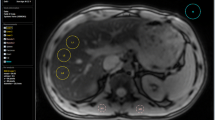

Assessment of iron overload is based on decreases in the T2 relaxation times induced in the liver due to the paramagnetic properties of iron. This acceleration of the T2 relaxation is proportional to the quantity of iron and leads to a decrease in the MRI signal intensity (SI) from the liver (Fig. 1).

In this method, an indication of LIC is obtained by calculating the ratio between the SI of the liver and the SI in paraspinal muscle that does not accumulate iron. The SI measurements are performed in the same slice using large regions of interest (ROIs), and GRE sequences are used due to their greater sensitivity to the paramagnetic effect of iron. In order to be able to quantify all levels of iron overload more than one sequence are necessary [24–28].

MRI sequences of the method of Gandon et al in three patients with different levels of LIC. a Patient without iron overload. b Patient with moderate iron overload. c Patient with high iron overload. d Scatterplots of L/M ratio and LIC for each MRI sequence. There is a maximal decrease in liver SI with most T2-weighted sequences. SE spin echo T1 sequence, PD proton density sequence (see [25])